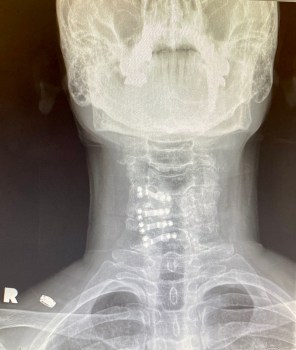

Screws and plates